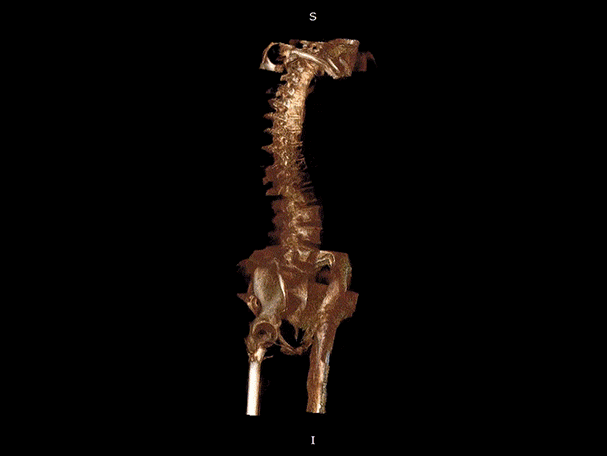

髋关节

颈椎

腰椎

VR体绘制重建